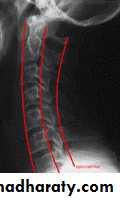

X-rays:

Cervical: 3 views.AP, lateral and open mouth.

Thoraco-lumbar: 2 views.

AP & lateral.

Flexion-Extension views.